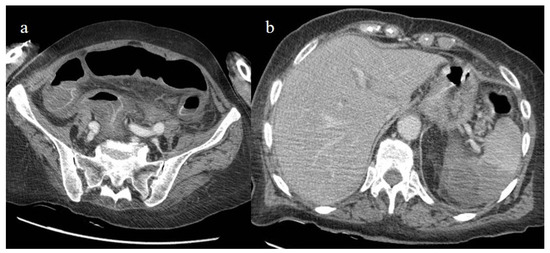

- Bonaffini, P.A.; Franco, P.N.; Bonanomi, A.; Giaccherini, C.; Valle, C.; Marra, P.; Norsa, L.; Marchetti, M.; Falanga, A.; Sironi, S. Ischemic and hemorrhagic abdominal complications in COVID-19 patients: Experience from the first Italian wave. Eur. J. Med. Res. 2022, 27, 1–9. [Google Scholar] [CrossRef]

- Peshevska-Sekulovska, M.; Boeva, I.; Sekulovski, M.; Zashev, M.; Peruhova, M. Gastrointestinal Ischemia—Stumbling Stone in COVID-19 Patients. Gastroenterol. Insights 2022, 13, 206–217. [Google Scholar] [CrossRef]

- Norsa, L.; Bonaffini, P.A.; Caldato, M.; Bonifacio, C.; Sonzogni, A.; Indriolo, A.; Valle, C.; Furfaro, F.; Bonanomi, A.; Franco, P.N.; et al. Intestinal ischemic manifestations of SARS-CoV-2: Results from the ABDOCOVID multicentre study. World J. Gastroenterol. 2021, 27, 5448–5459. [Google Scholar] [CrossRef]

- Singh, B.; Kaur, P. COVID-19 and acute mesenteric ischemia: A review of literature. Hematol. Transfus. Cell Ther. 2020, 43, 112–116. [Google Scholar] [CrossRef]

- Bhayana, R.; Som, A.; Li, M.D.; Carey, D.E.; Anderson, M.A.; Blake, M.A.; Catalano, O.; Gee, M.S.; Hahn, P.F.; Harisinghani, M.; et al. Abdominal Imaging Findings in COVID-19: Preliminary Observations. Radiology 2020, 297, E207–E215. [Google Scholar] [CrossRef]

- Caruso, D.; Zerunian, M.; Pucciarelli, F.; Lucertini, E.; Bracci, B.; Polidori, T.; Guido, G.; Polici, M.; Rucci, C.; Iannicelli, E.; et al. Imaging of abdominal of abdominal complications of COVID-19 infection. BJR Open 2021, 2, 20200052. [Google Scholar] [CrossRef]

- Ojha, V.; Mani, A.; Mukherjee, A.; Kumar, S.; Jagia, P. Mesenteric ischemia in patients with COVID-19: An updated systematic review of abdominal CT findings in 75 patients. Abdom. Imaging 2021, 47, 1565–1602. [Google Scholar] [CrossRef]

- Boraschi, P.; Giugliano, L.; Mercogliano, G.; Donati, F.; Romano, S.; Neri, E. Abdominal and gastrointestinal manifestations in COVID-19 patients: Is imaging useful? World J. Gastroenterol. 2021, 27, 4143–4159. [Google Scholar] [CrossRef]

- Keshavarz, P.; Rafiee, F.; Kavandi, H.; Goudarzi, S.; Heidari, F.; Gholamrezanezhad, A. Ischemic gastrointestinal complications of COVID-19: A systematic review on imaging presentation. Clin. Imaging 2020, 73, 86–95. [Google Scholar] [CrossRef] [PubMed]

- Gupta, A.; Sharma, O.; Srikanth, K.; Mishra, R.; Tandon, A.; Rajput, D. Review of Mesenteric Ischemia in COVID-19 Patients. Indian J. Surg. 2022, 85, 313–321. [Google Scholar] [CrossRef]

- Reginelli, A.; Genovese, E.; Cappabianca, S.; Iacobellis, F.; Berritto, D.; Fonio, P.; Coppolino, F.; Grassi, R. Intestinal Ischemia: US-CT findings correlations. Crit. Ultrasound J. 2013, 5, S7. [Google Scholar] [CrossRef]

- Paul, T.; Joy, A.R.; Alsoub, H.A.R.S.; Parambil, J.V. Case Report: Ischemic Colitis in Severe COVID-19 Pneumonia: An Unforeseen Gastrointestinal Complication. Am. J. Trop. Med. Hyg. 2021, 104, 63–65. [Google Scholar] [CrossRef]

- Uhlenhopp, D.J.; Ramachandran, R.; Then, E.; Parvataneni, S.; Grantham, T.; Gaduputi, V. COVID-19-Associated Ischemic Colitis: A Rare Manifestation of COVID-19 Infection—Case Report and Review. J. Investig. Med. High Impact Case Rep. 2022, 10, 1–6. [Google Scholar] [CrossRef]

- Krejčová, I.; Berková, A.; Kvasnicová, L.; Vlček, P.; Veverková, L.; Penka, I.; Zoufalý, D.; Červeňák, V. Ischemic Colitis in a Patient with Severe COVID-19 Pneumonia. Case Rep. Gastroenterol. 2022, 16, 526–534. [Google Scholar] [CrossRef]

- Alratrout, H.; Debroux, E. Acute right-sided ischemic colitis in a COVID-19 patient: A case report and review of the literature. J. Med. Case Rep. 2022, 16, 1–5. [Google Scholar] [CrossRef]